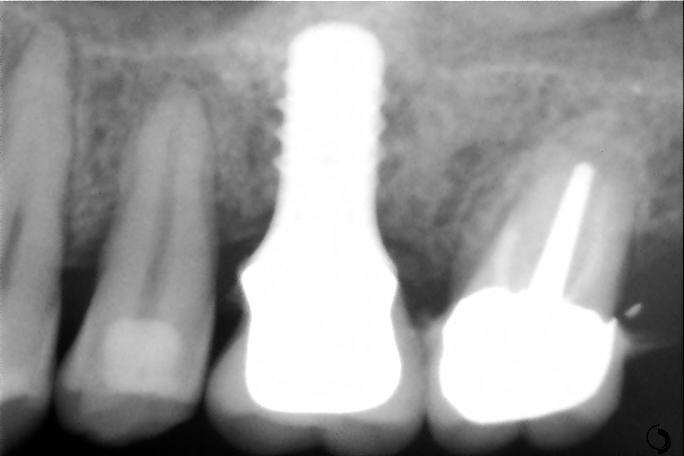

Le sinus lift (accès par voie latérale) : lorsqu’il manque de l’os en arrière du maxillaire supérieur, on accède au sinus par une paroi latérale et on le comble avec nos matériaux. Cela augmente la hauteur osseuse disponible.

Le push-back (apport par voie crestale) : cette méthode permet d’apporter de l’os par le trou de forage lors de la pose de l’implant.